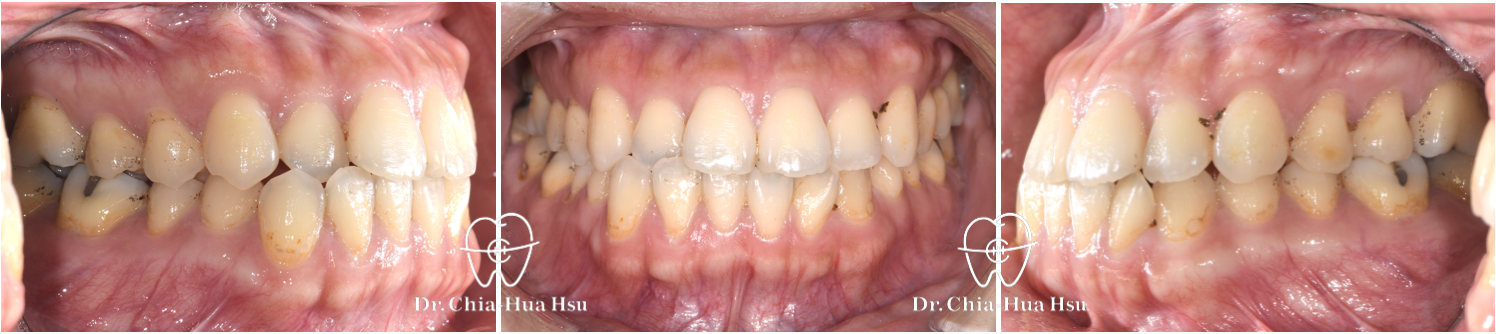

治療前

治療後